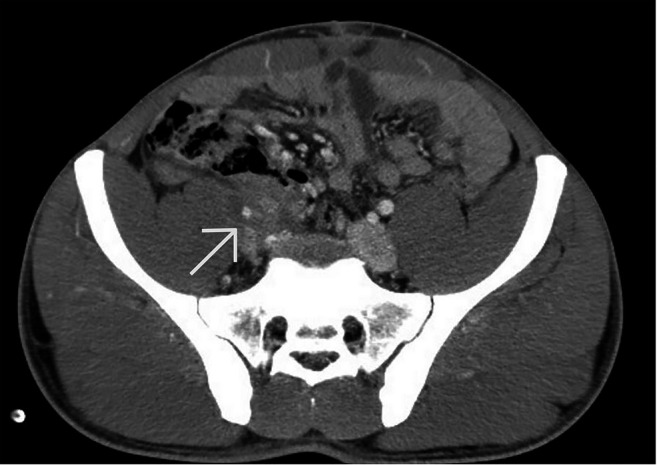

Background/aim: Immunoglobulin G4-related disease (IgG4-RD) is a systemic, immune-mediated condition characterized by fibroinflammatory lesions affecting multiple organs. When localized in the retroperitoneum, it may mimic malignancy and often leads to surgical intervention. We report the case of a 21-year-old male with retroperitoneal IgG4-RD and review the relevant literature, emphasizing the diagnostic challenges and importance of differential diagnosis.

Results: Of 74 articles retrieved, 22 met the inclusion criteria, totaling 23 patients including our case. The mean age was 62 years, with a male predominance (65%). The left ureter was most commonly involved (52%). Frequent symptoms included localized abdominal pain (61%) and hydronephrosis (96%). Imaging often suggested malignancy, leading 74% of patients to undergo surgery. Histopathology confirmed IgG4-RD in all cases, though only 30% showed IgG4 immunohistochemical positivity.

Conclusion: Retroperitoneal IgG4-RD closely mimics malignancy, posing significant diagnostic challenges. Elevated serum IgG4 levels and tissue biopsy are critical for accurate diagnosis. IgG4-RD should be considered in patients with unexplained retroperitoneal masses to avoid unnecessary surgery and ensure appropriate treatment.